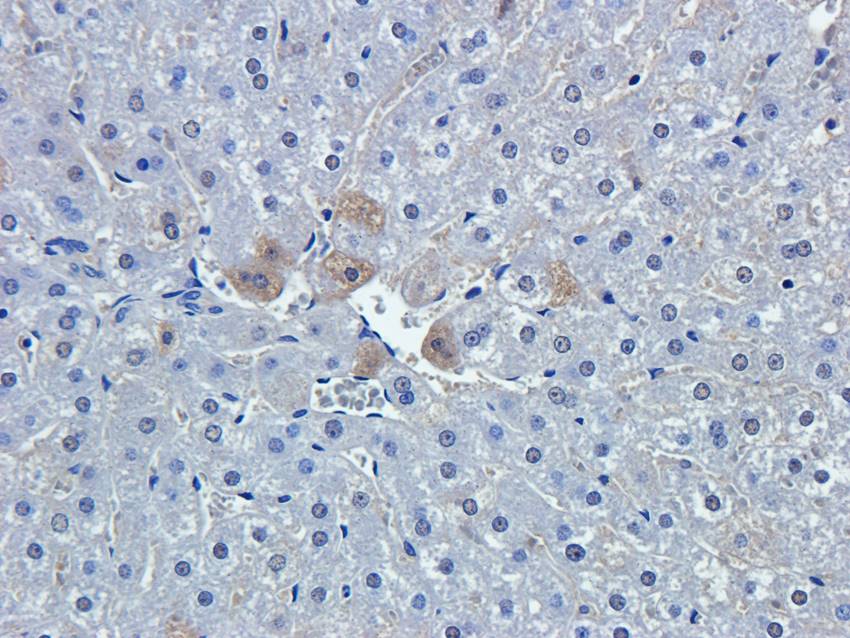

100 μg - OPG antibody [orb247239]Featured

ELISA, ICC, IF, IHC-P, WB

Bovine, Canine, Human, Mouse, Rat

Rabbit

Polyclonal

Unconjugated

100 μg